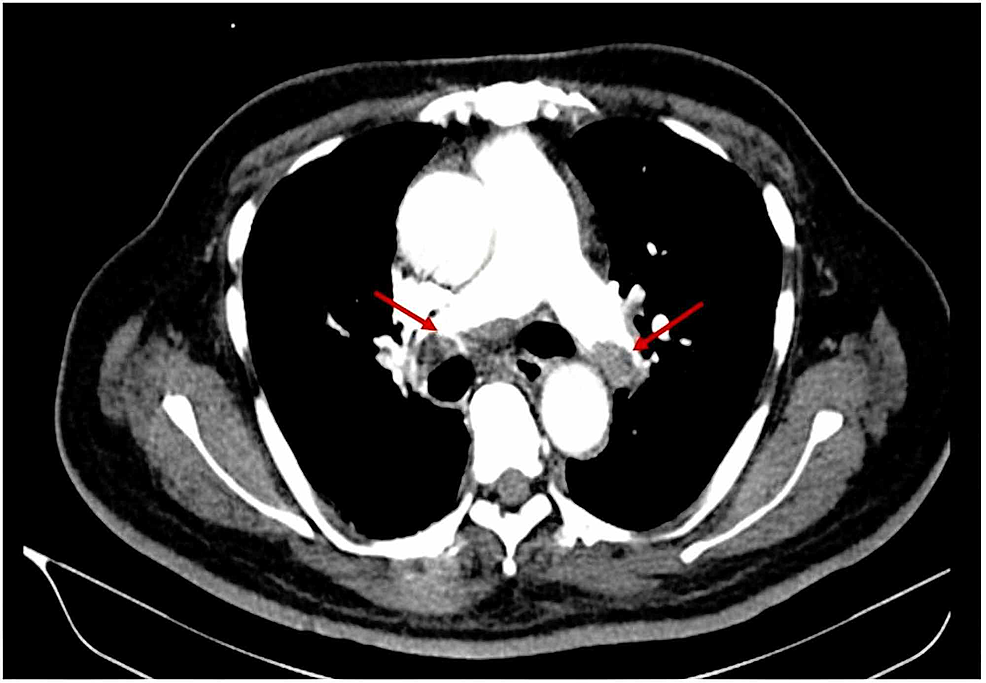

Pulmonary embolism (pe) is often difficult to diagnose because the symptoms of pe are a lot like those of many other conditions and diseases. Pulmonary embolism (pe) is a blockage of an artery in the lungs by a substance that has moved from elsewhere in the body through the bloodstream (embolism). If you have symptoms suggestive of a pulmonary embolism, such as sudden, unexplained shortness of breath or chest pain, it is important that you get checked by a physician.

Pulmonary embolism will produce symptoms such as sharp chest pain, sudden shortness of breath, and a cough that.

Pulmonary embolism (pe) is a blockage of an artery in the lungs by a substance that has moved from elsewhere in the body through the bloodstream (embolism). Pleurisy, which is sharp chest pain with a deep breath; However, today i was sitting down and my chest hurt in that spot followed by the pain when breathing for a few mins. Pulmonary embolism (pe) is often difficult to diagnose because the symptoms of pe are a lot like those of many other conditions and diseases.